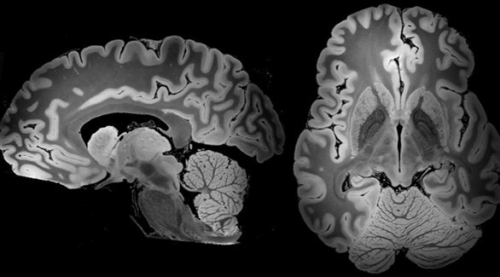

يتراكم الحديد في الدماغ مع التقدم في العمر

ويتزايد تراكم الحديد في الدماغ مع التقدم في العمر، وتوجد أدلة على تأثير ذلك السلبي على وظائف الدماغ.